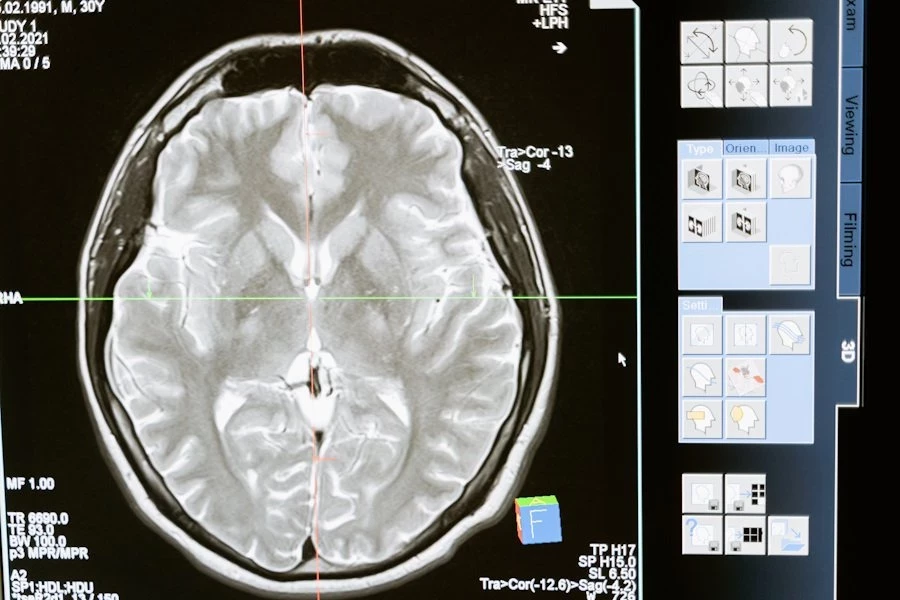

В исследовании приняли участие 2 667 человек со средним возрастом 68 лет, преимущественно латиноамериканского происхождения. В рамках эксперимента они прошли домашнее тестирование сна, позволяющее зафиксировать остановки дыхания и замедления. На основе этих данных участников разделили на три группы: без нарушений дыхания, с лёгкими нарушениями и с тяжёлыми нарушениями. Через 10 лет все добровольцы прошли сканирование мозга.

Результаты анализа показали, что у людей с тяжёлыми нарушениями дыхания объём гиппокампа — области мозга, ответственной за память и мышление, — оказался на 0,24 кубического сантиметра больше, чем у тех, кто спал без проблем. Более того, каждое дополнительное нарушение дыхания приводило к увеличению объёма гиппокампа на 0,006 кубического сантиметра.

Ещё одна важная находка связана с уровнем кислорода в крови. Учёные выяснили, что снижение кислорода во время сна связано с увеличением гиппокампа и повреждением белого вещества мозга. Повреждённые области белого вещества, согласно исследованию, могут нарушать взаимодействие между различными участками мозга.